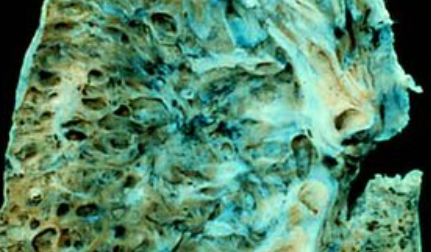

폐섬유증은 폐 조직이 점차 굳어지면서 호흡장애를 일으키는 질환인데요. 폐섬유화증은 폐섬유증의 한 종류로, 폐 조직이 딱딱해지는 현상을 의미합니다. 이러한 변화는 폐에 염증이 생겼다가 아무는 것이 반복되면서 마치 상처가 굳은살과 흉터를 만드는 것과 비슷한데요.

폐섬유증과 폐섬유화증의 주요 원인은 다양합니다. 그러나 가장 흔한 원인 중 하나는 만성 염증입니다. 만성 염증은 폐 조직에 지속적인 염증 반응을 유발하며, 이는 폐 조직의 손상과 염증 반응이 반복되면서 섬유화 과정을 유발합니다. 이 과정에서 폐 조직 내 결합조직이 비정상적으로 증식하고 딱딱하게 굳어지는 현상이 나타나게 됩니다.